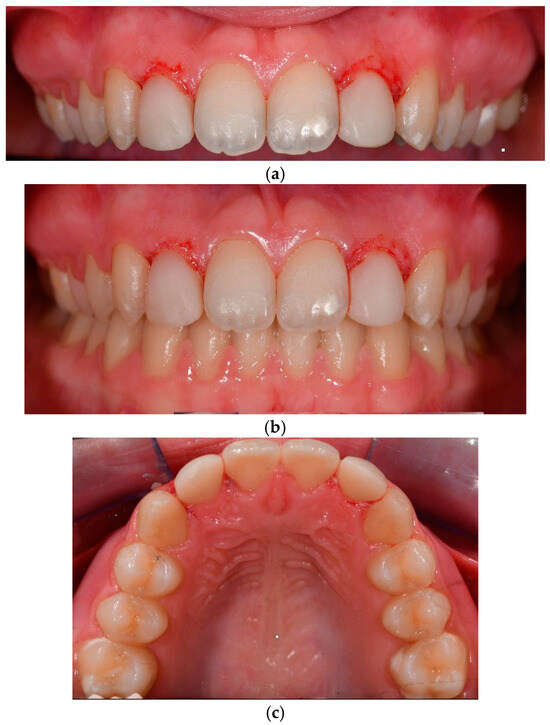

2.1. Case 1

2.1.1. Patient Presentation

2.1.2. Clinical Findings

2.1.3. Diagnosis and Assessment

2.1.4. Intervention Types Considered

2.1.5. Therapeutic Intervention

2.2. Case 2